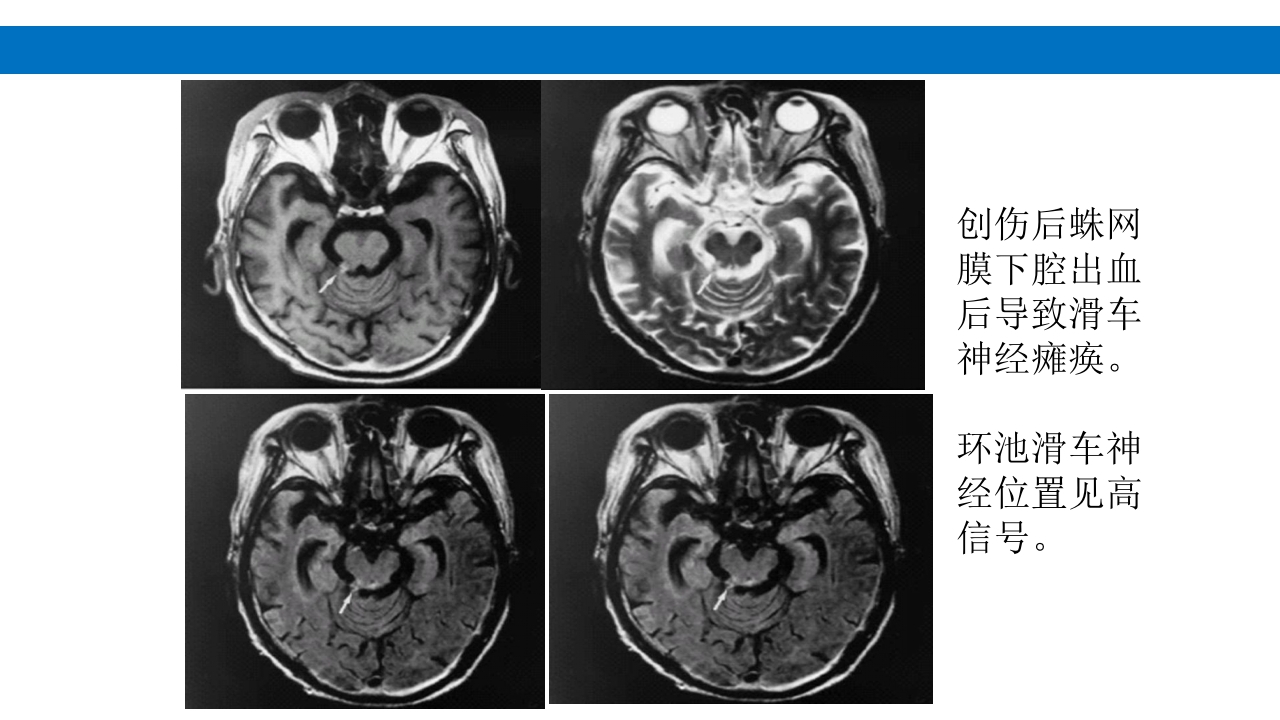

颅脑损伤的并发症及后遗症 讲解人:xxx 20XX年x月x日 1.颅骨骨髓炎 病因:为头皮软组织、中耳、乳突和副鼻窦等处炎性感染而经导 血管侵入颅骨内或颅脑开放伤感染所引起,亦可由菌血症后发生 的细菌栓子由血运转移至颅骨内。 影像学表现: 头部CT: 1.表现为不规则的蜂窝状骨质破坏区,主要位于板障,亦可累 及内外板。 2.破坏区内可见高密度的米粒状细小的高密度死骨。 3.周边可见骨质硬化增生,颅板外无骨膜反应。 4.局部的头皮可见软组织肿胀。 头部MRI: 由于受累部位细胞成分和水量增多,T1WI为低信号, T2WI为高信号,急性期边界不清,慢性期病灶局限, 边界清晰。MRI显示骨质破坏没有CT效果好。 治疗: 除应用抗菌药物控制感染外,当感染局限或已有死骨形成后, 应行手术切除感染...